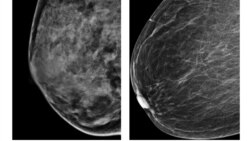

Ko'krak rakidan shifo izlab-1-qism-Navbahor Imamova